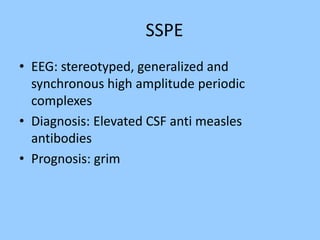

1. The document discusses EEG patterns and findings in various neurological conditions seen in children. It includes descriptions of normal EEG findings as well as abnormal patterns seen in conditions like absence seizures, West syndrome, benign childhood epilepsy with centrotemporal spikes, Lennox-Gastaut syndrome, non-convulsive status epilepticus, subacute sclerosing panencephalitis, and herpes encephalitis.

2. Case studies are presented with clinical histories and EEG findings to illustrate different pathologies. Treatment options are also mentioned for many of the conditions.